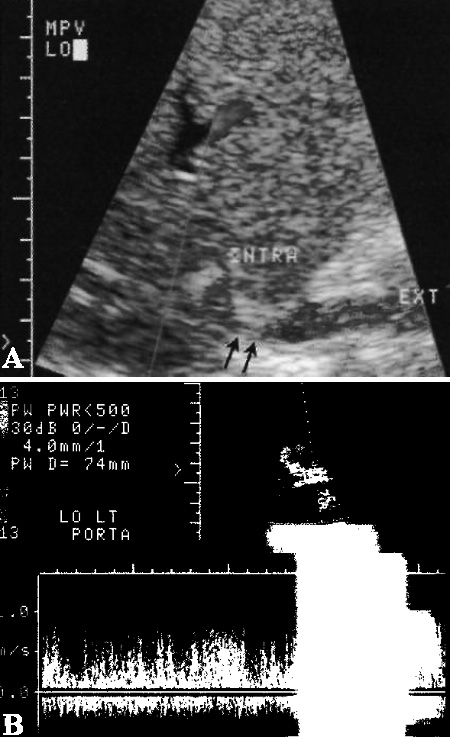

Стеноз или тромбоз воротной вены считается редким посттрансплантационным осложнением (< 2% случаев). Чаще возникает у детей и, во многих случаях, сопровождается нарушением функции печеночной артерии. При этом, как правило, выявляют аномальную турбулентность в зоне наложения анастомоза воротной вены, однако значительный стеноз со сниженным портальным кровотоком диагностируют редко (фото 3).

Фото 3. Стеноз воротной вены. А –на ультразвуковом изображении, полученного у ребенка после трансплантации печени, стрелками обозначено сужение просвета воротной вены. В – смешанный многоцветовой поток (выраженная турбулентность) наблюдается непосредственно позади стеноза